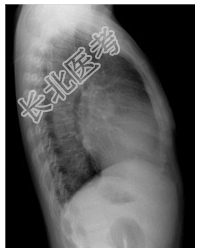

- [材料题] 患者,女性,48岁,劳累后心悸、气促2年余,加重伴呼吸困难1周。查体:患者颧部潮红,心尖区可闻及舒张期隆隆样杂音,第二心音亢进、分裂,双肺可闻及细湿啰音。心界向两侧扩大。行胸部平片检查。

- 简答题1、诊断及依据是什么?

- 简答题2、鉴别诊断有哪些?